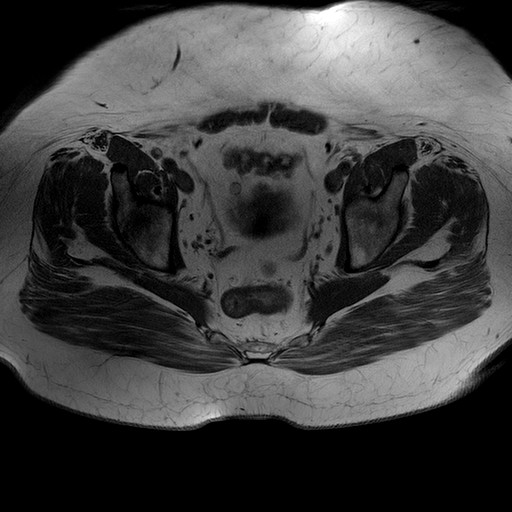

Esami: RMN BACINO

T1W_TSE

Evidenti e simmetriche alterazioni osteofitosiche in regione coxo femorale con riduzione delle rime articolari. Degenerazione completa del cercine glenoideo. Non attuali segni di versamento articolare. Non segni di edema osseo che escludono attuale algodistrofia od osteonecrosi. Lieve e simmetrica riduzione del trofismo della muscolatura glutea.